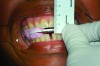

A patient’s candidacy for oral appliance therapy is determined based on careful evaluation of the dentition, periodontium, oral soft tissues, masticatory muscles, and TMJ. A sufficient number of teeth (ideally, eight in each arch) without decay or faulty restorations and of sufficient height to retain the oral appliance must be present, although mandibular advancement devices (MADs) can be supported by dental implants (Figure 1).1 Any active periodontal disease should be treated. The alveolar bone level should be adequate to withstand forces applied by the appliance. The presence of temporomandibular disorders per se is not a contraindication to oral appliance therapy. However, some patients will not be able to tolerate jaw advancement, while others may benefit from it.2 Based on the sleep study report and the orofacial examination, the dentist determines whether the patient is a good, guarded, or poor candidate for MAD therapy.

Fig 1. Edentulous patient treated with a MAD (SUAD Herbst appliance: http://www.strongdental.com/). The upper component is fit and contoured similar to the patient’s full upper denture. The lower component is retained by two dental implants with Locator® abutments (http://www.zestanchors.com/ ).

Fig 1. Edentulous patient treated with a MAD (SUAD Herbst appliance, strongdental.com). The upper component is fit and contoured similar to the patient’s full upper denture. The lower component is retained by two dental implants with Locator® abutments (zestdent.com).

Figure 1